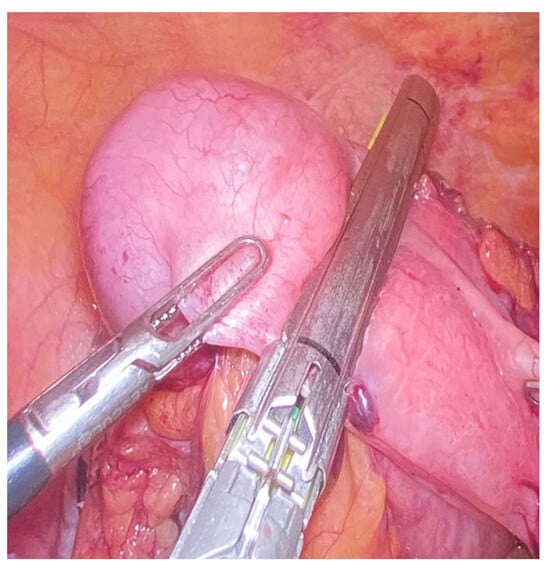

Figure 5. Mucocele of the appendix without perforation during laparoscopic surgery. There is a partial dilatation of the appendix and a healthy appendicular base.

Figure 6. Radical appendectomy including appendiceal mesentery and cecal bases with linear stapler.

Mucocele of the appendix refers to a dilated mucin-containing appendix. This term is mainly used by clinicians and radiologists (Figure 1, Figure 2, Figure 3 and Figure 4). It is necessary to distinguish “true mucocele” from a mucinous adenoid neoplasm [7]. The term mucocele was first used by Karl Freiherr von Rokitansky in 1842. Two years later, Werth used the term pseudomyxoma peritonei [4]. The clinical signs are minimal or often completely absent. The rupture of the mucocele can also be asymptomatic. Mucocele may be found on ultrasound or via a regular gynecological examination. A CT scan confirms the diagnosis. Treatment consists of the surgical removal of the dilated appendix, often together with the surrounding part of the cecum (Figure 5, Figure 6 and Figure 7). This approach is curative if there is no rupture or presence of tumor cells on the peritoneal surface. The diagnosis is confirmed through pathological examination of the specimen (Figure 8).